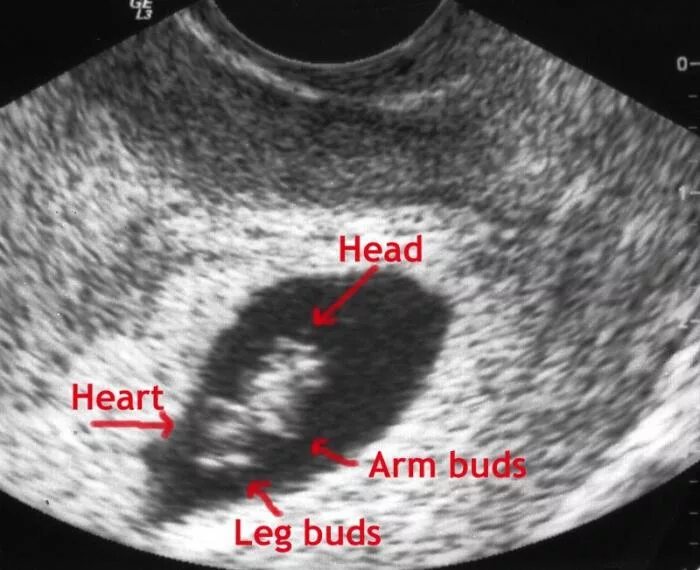

Седьмая неделя